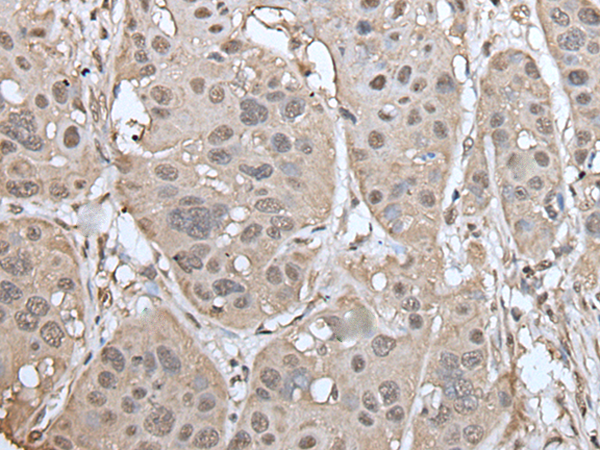

ELISA, IHC

IHC positive control:

Human tonsil and human esophagus cancer

IHC Recommend dilution:

40-250